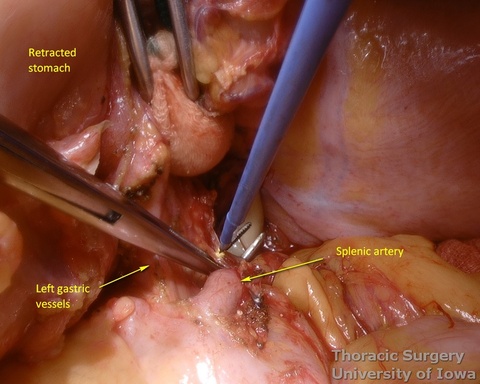

- Once the stomach is mobilized and reflected anteriorly, the left gastric vascular pedicle is identified and dissected close to the origin for adequate lymphadenectomy. Care is taken to not injure splenic artery and pancreas.

- Postradiation adhesions may be dense.

- Left gastric vessels are divided with an endoscopic linear cutting stapler proximally, including all adjacent lymph nodes in the specimen.